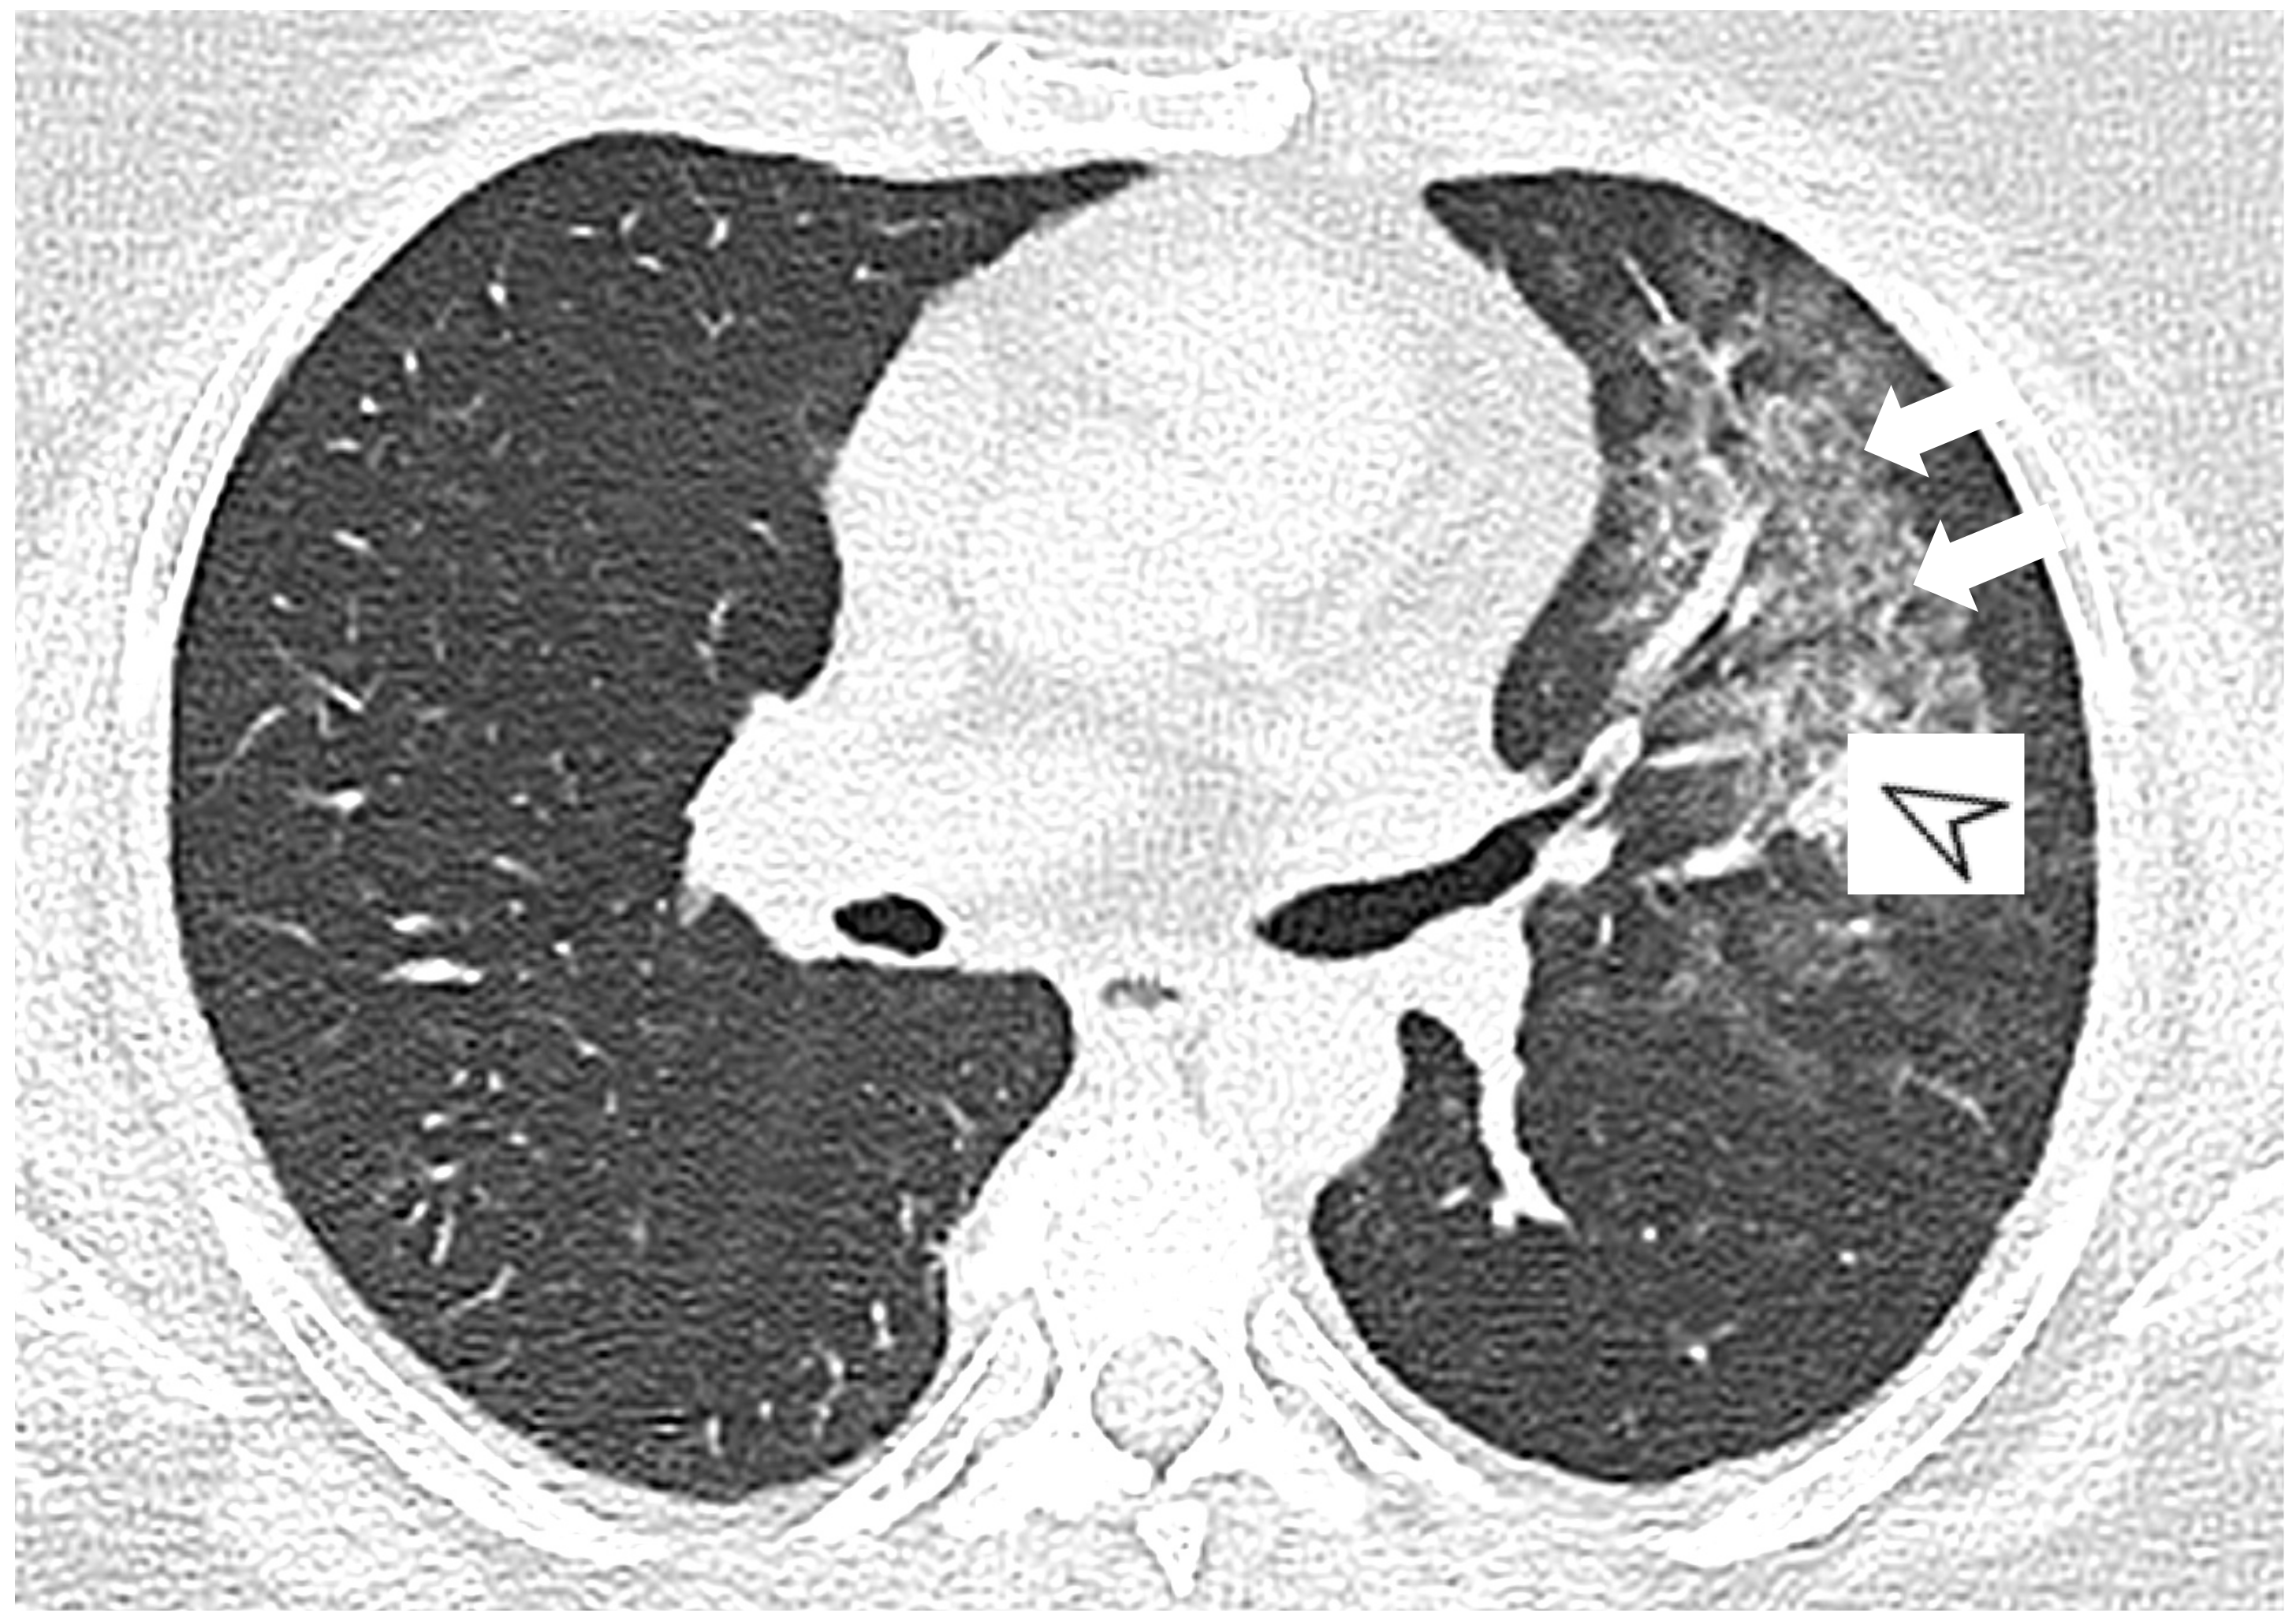

2.5. Eosinophilic Granulomatosis with Polyangiitis (EGPA-Churg-Strauss)

| EGPA | Migrant GGOs, transient consolidation, irregular bronchial wall thickening, small nodules with peribronchial and centrilobular distribution, pleural effusion. |